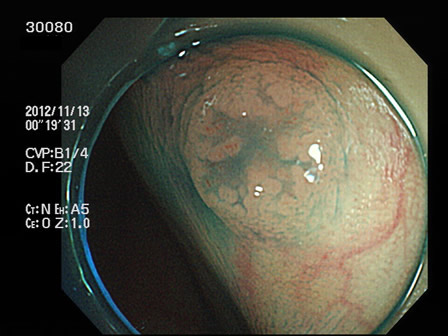

上記100名より抽出した平坦・陥凹型腺腫(=癌化の危険が高いが見落としやすい病変)の内視鏡写真

30001 30005 30008 30014 30016 30019 30020 30022 30023 30024 30025 30026 30027 30028 30029 30031 30033 30034 30036 30038 30044 30045 30047 30049 30051 30053 30055 30056 30057 30058 30059 30060 30066 30069 30072 30073 30074 30076 30077 30078 30079 30080 30081 30082 30083 30084 30085 30087 30088 30092 30097 30098・・・・・・・の52名